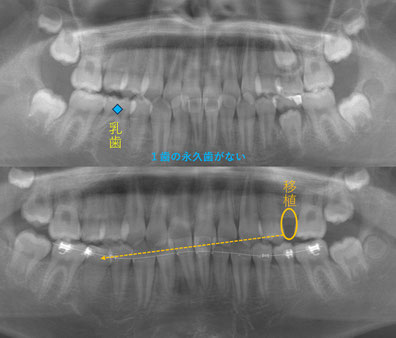

上顎前突(いわゆる出っ歯)の患者さん、13歳。

左上の5番目の歯を右下の5番目に移植しています。移植後2か月目で神経がつながっている、つまり生きている反応が検査で出てきました。

今は、抜いた歯の隙間を埋めるように歯を移動させることで前歯も引っ込みました。よく噛めるようになっています。